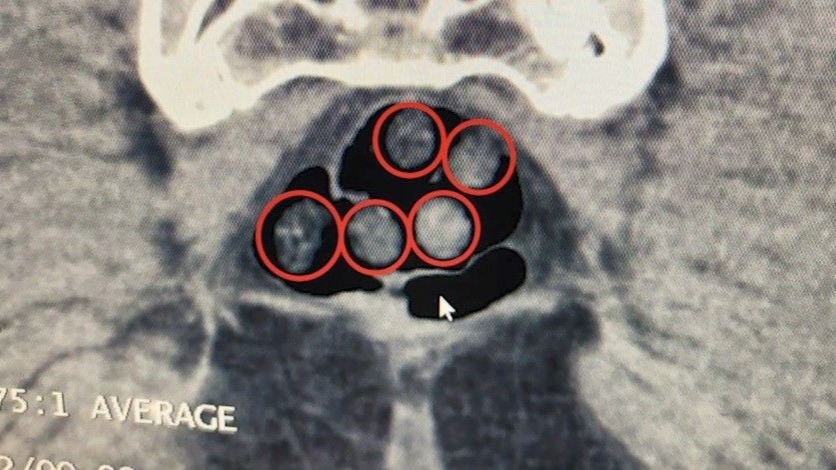

Bitlis Valiliğinden yapılan açıklamada, Bitlis Emniyet Müdürlüğü Narkotik Suçlarla Mücadele Şube Müdürlüğü ve İstihbarat Şube Müdürlüğü ekiplerinin uyuşturucu ile mücadele kapsamında yürüttüğü iki ayrı titiz çalışmanın başarıyla sonuçlandırıldığını bildirdi. Açıklamada, "Tatvan’da durdurulan çekici üzerindeki araçta yapılan aramada; 734 gram metamfetamin maddesi ele geçirildi. Olay ile ilgili 2 şahıs gözaltına alındı. Yine Tatvan’da durdurulan bir otobüste yolcu olarak seyahat eden yabancı uyruklu 2 şahıs gözaltına alındı. Tatvan Devlet Hastanesinde yapılan röntgen ve tomografi incelemelerinde, şahısların mide ile bağırsaklarında çok sayıda yabancı cisim tespit edildi. Yapılan tıbbi müdahale ile şahısların yuttuğu 14 kapsül ve üzerlerinden 36 kapsül olmak üzere toplam 50 kapsül 385 gram metamfetamin maddesi ele geçirildi. Her iki olayda da uyuşturucu madde imal ve ticareti suçundan gözaltına alınan 4 şahıstan 3’ü çıkarıldığı adli mercilerce tutuklandı. Hemşehrilerimizin huzuru ve güvenliği için uyuşturucu madde imalatı, kaçakçılığı ve kullanımına karşı yürütülen kararlı mücadelemiz devam edecektir" denildi.